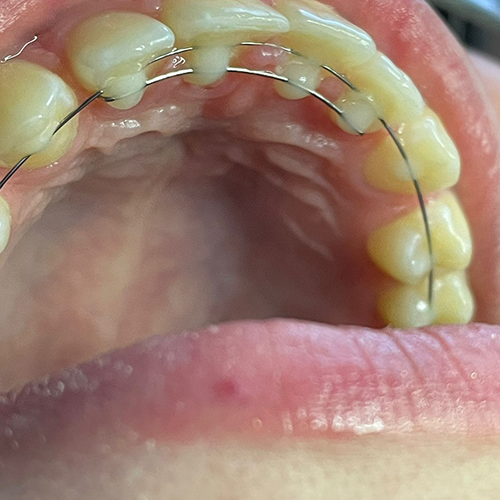

Comprueba en la práctica cómo el conocimiento se transforma en resultados reales a través de los casos de nuestros alumnos.

SALA DE PROCEDIMIENTOS

Siga clases prácticas y la evolución de casos clínicos reales directamente desde la clínica del Dr. Ary Nunes.